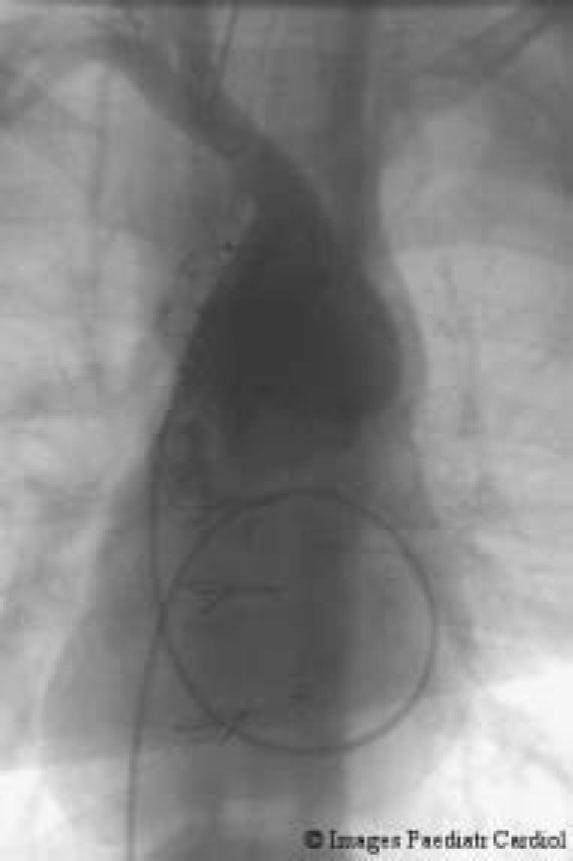

全腔静脉肺动脉连接术前先天性心脏病的心脏导管评估

Cardiac catheter assessment of congenital heart disease prior to total cavopulmonary connection.

This paper summarises the rationale behind cardiac catheter assessment prior to surgical completion of the Fontan circulation in hearts with univentricular pathology.

摘要